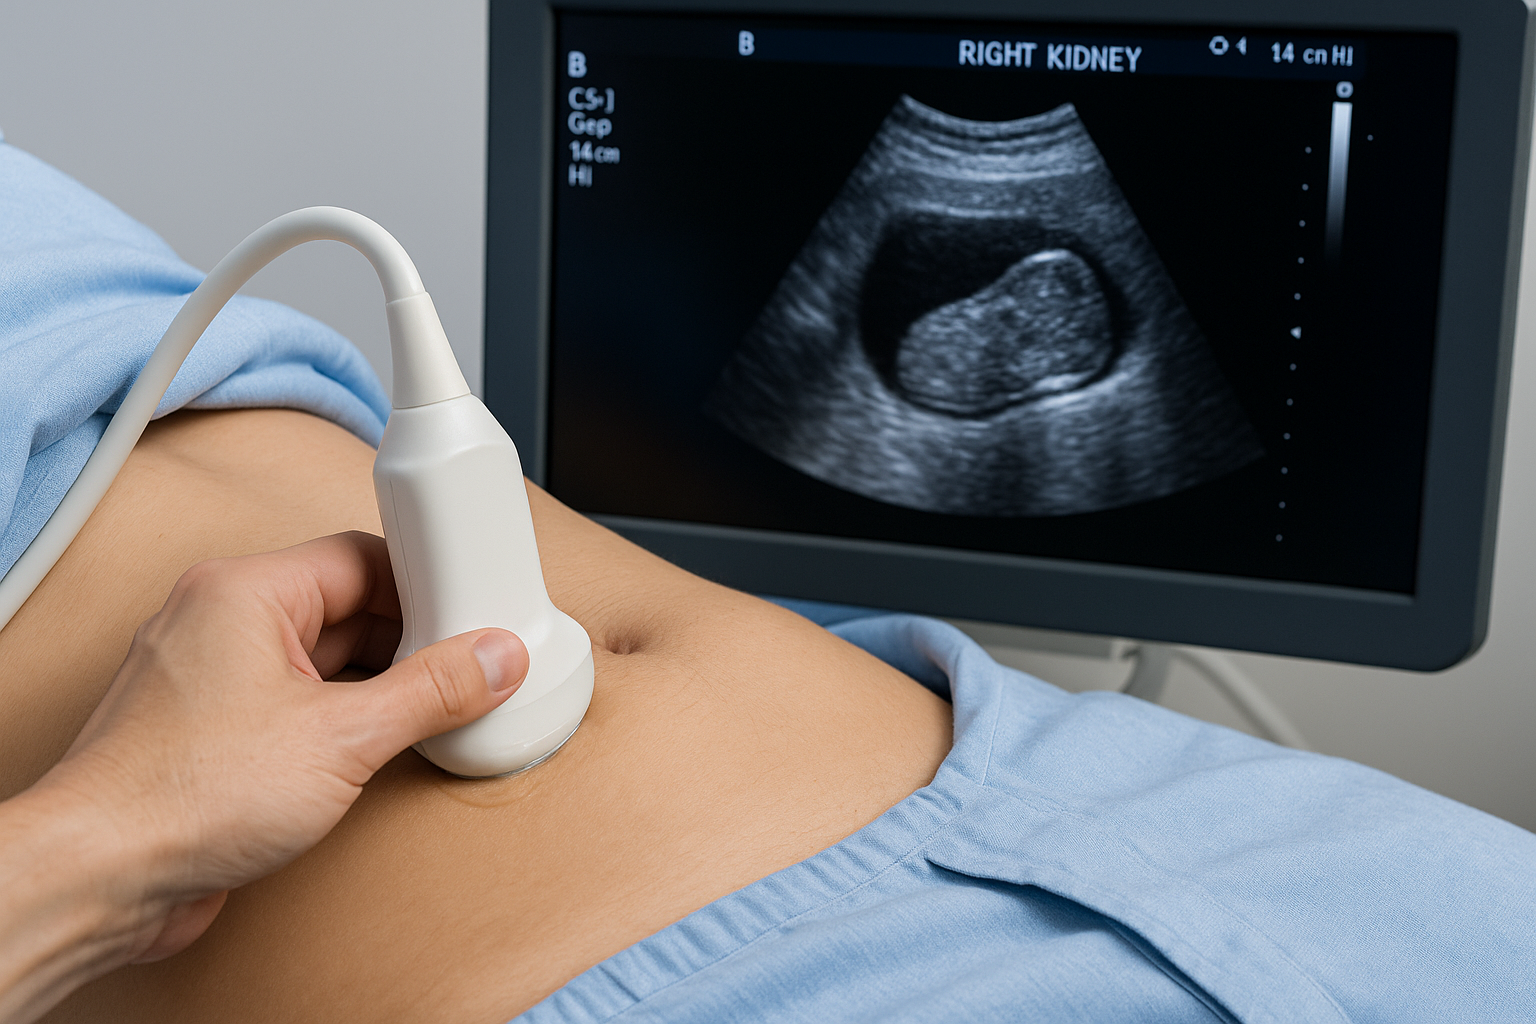

Renal

Ultrasound of the kidney (renal) arteries to check for narrowing that can affect blood pressure and kidney function. Gel is placed on the abdomen and a Doppler probe measures blood flow.